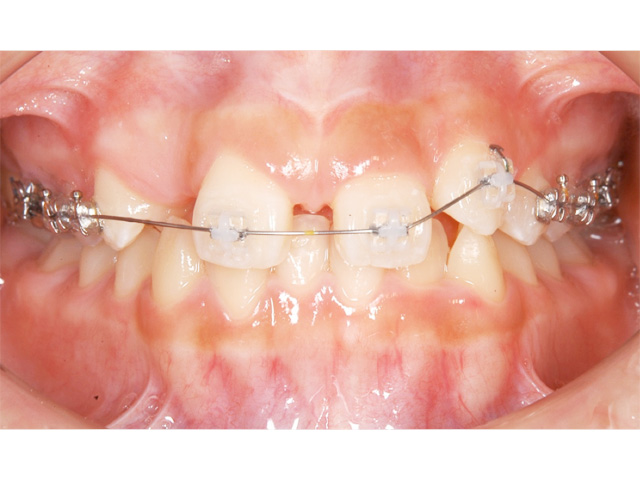

お口の天井部分を麻酔して開き、犬歯にフックをつけて矯正装置を用いて適正な位置まで移動させました。

約2年半の矯正治療で、とてもキレイな歯ならびになり、自信にあふれる輝くような笑顔を得ることができました。